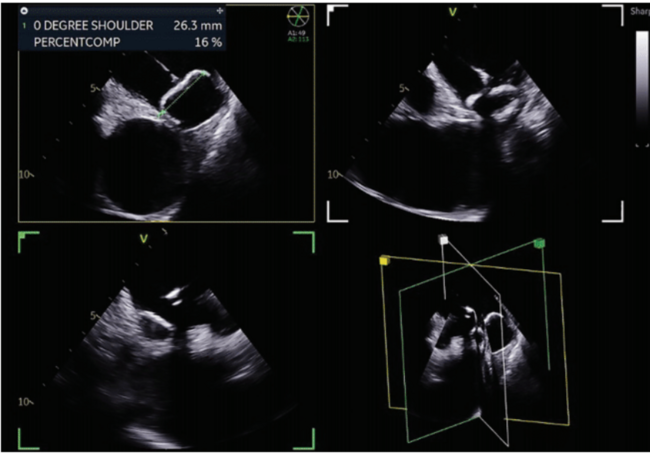

The initial positioning of the LAAO sheath in the appendage (Figure 5, Video 5), the deployment of the LAAO device, the tug test (Figure 6, Video

6), the measurements for compression (Figure 7), and the assessment for possible flow around the device (Figure 8, Video 7) can all be done in the 2D ICE views in a similar manner as TEE. All the available 4D ICE catheters allow for MPR to create a live 3D image that may be helpful in navigating a challenging anatomy or to provide additional perspective on the size and shape of the LAAO device in the appendage (Figure 9, Video 8). Once the device is deployed and both the LAAO sheath and ICE catheter are returned to the RA, the final step is to return the ICE catheter to the right ventricle and confirm the absence of any significant pericardial effusion. Once catheters are removed from the body, use of a closure device or a subcutaneous figure-of-8 suture is recommended to facilitate faster patient recovery.

Figure 5/Video 5.

Initial positioning of the LAAO sheath in the LAA in a multiplanar view, using NUVISION catheter (Biosense Webster, Inc, a Johnson & Johnson company).